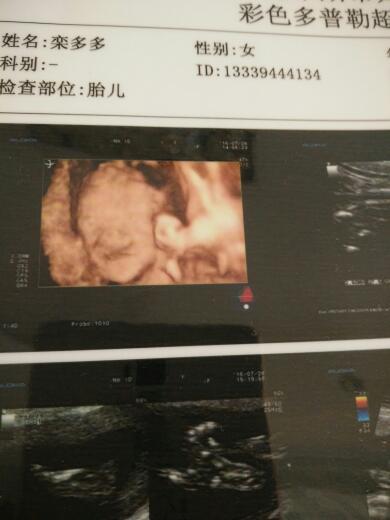

帮我看看我家孩子是不是兔唇,昨天做的四维,感觉大夫不是很负责,我看着像兔唇,可是大夫说照的不清晰

帮我看看我家孩子是不是兔唇,昨天做的四维,感觉大夫不是很负责,我看着像兔唇,可是大夫说照的不清晰说照的不好,看不出来什么,那他那些诊断能是正确的吗,烦死了

检查结果提示:‘’上唇连线未见中断‘’,这种情况就是正常了。敢绣如果你对超声结果检查结果有异议,也耻战建议换一个大的医院再做一次检查。原则上四维检查准确率很高。过梅键